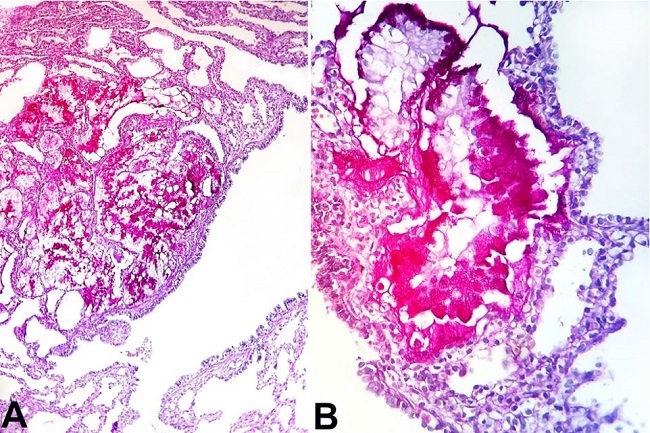

Histological examination of the right lung stained with hematoxylin-eosin (H&E) and Periodic Acid Schiff (PAS) revealed a proliferation of the terminal respiratory structures forming cysts that were lined with ciliated pseudostratified epithelium with polypoid projections of the mucosa, small cartilage foci in the wall of the bronchial structures ( Figure 3A, 3B ), clusters of goblet cells, and mucinous glands ( Figure 4A and 4B ). The left lung showed an immature parenchyma with the predominance of collapsed alveoli. However, cartilage around the bronchi was present.

The diagnosis of type I CPAM, in this case, was based on clinical presentation and macroscopic finding characterized by multiple large cysts, which was confirmed by histological examination, and which demonstrated cysts with ciliated pseudostratified epithelial lining with bronchiolar differentiation, a cluster of goblet cells, mucinous glands, and small cartilage foci. The risk of respiratory distress at birth is up to 30% in cases of type I CPAM.1